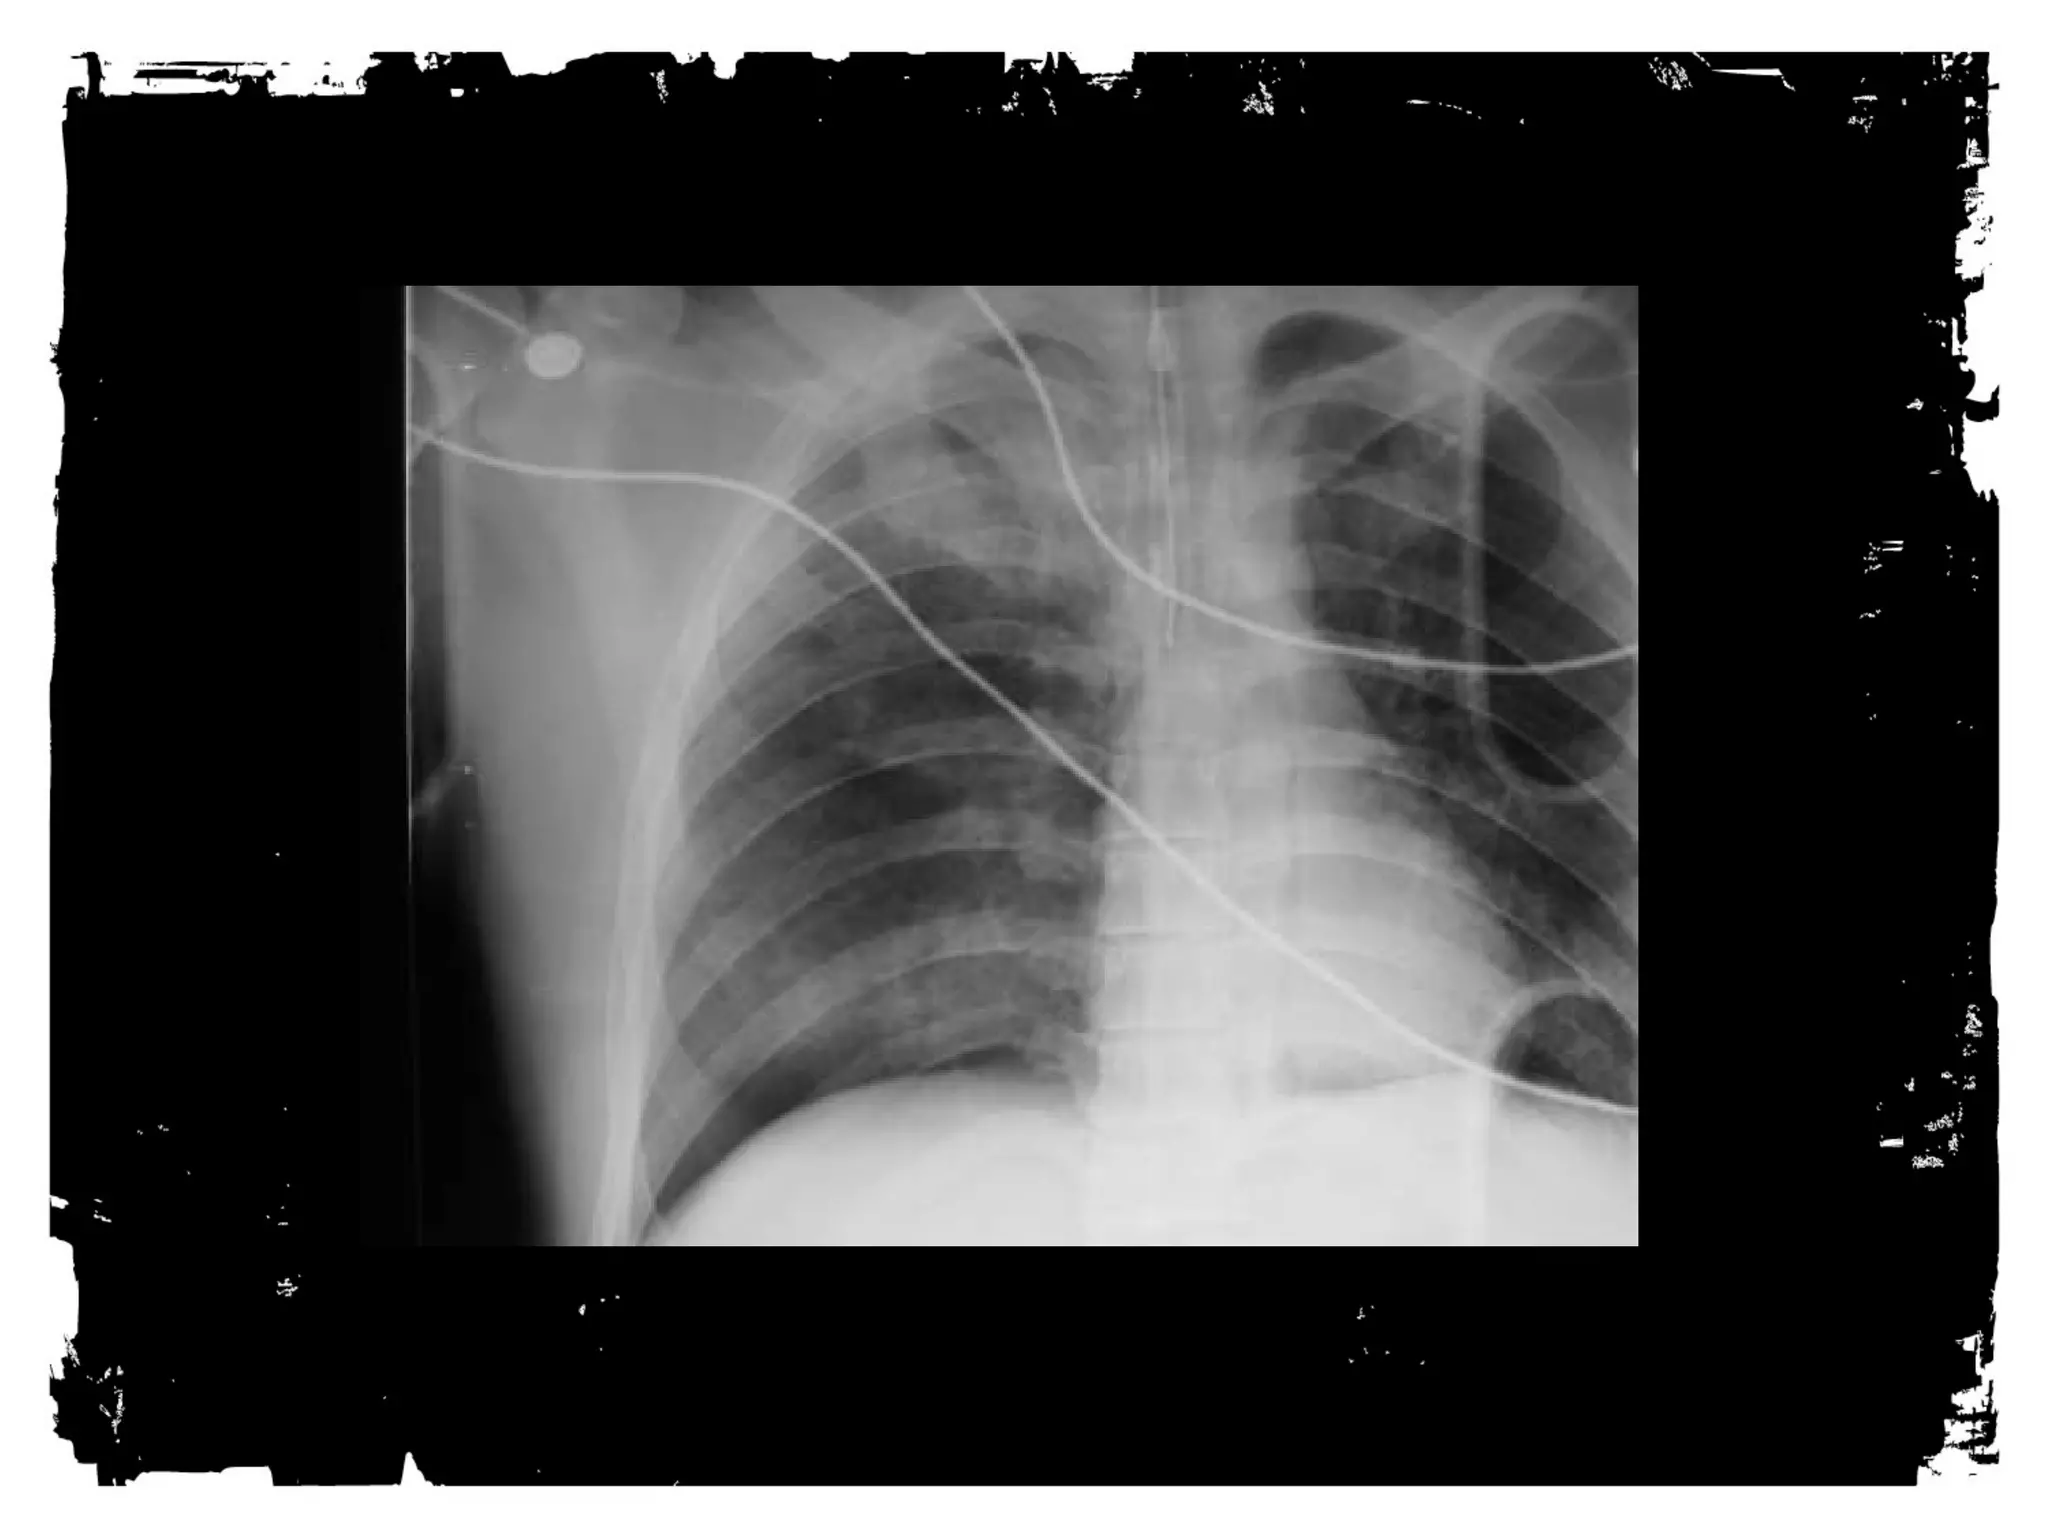

HEMOTHORAX

• Venous or arterial bleeding

• 60% controlled by chest tube,

40% need operative

management

• Can miss hundreds of cc’s on

supine film

• Can be tension

PENETRATING TRAUMA

Gun-shot wounds:

Caliber, weight, construction of bullet

Velocity

Tissue impacted

Knife wounds:

All low energy, small diameter wounds. Frequently,

superficial stab or slash.

Look for lung laceration, pneumothorax, hemothorax,

pneumomediastinum, abnormal contour of

mediastinum or heart.

Path of wound is straight.